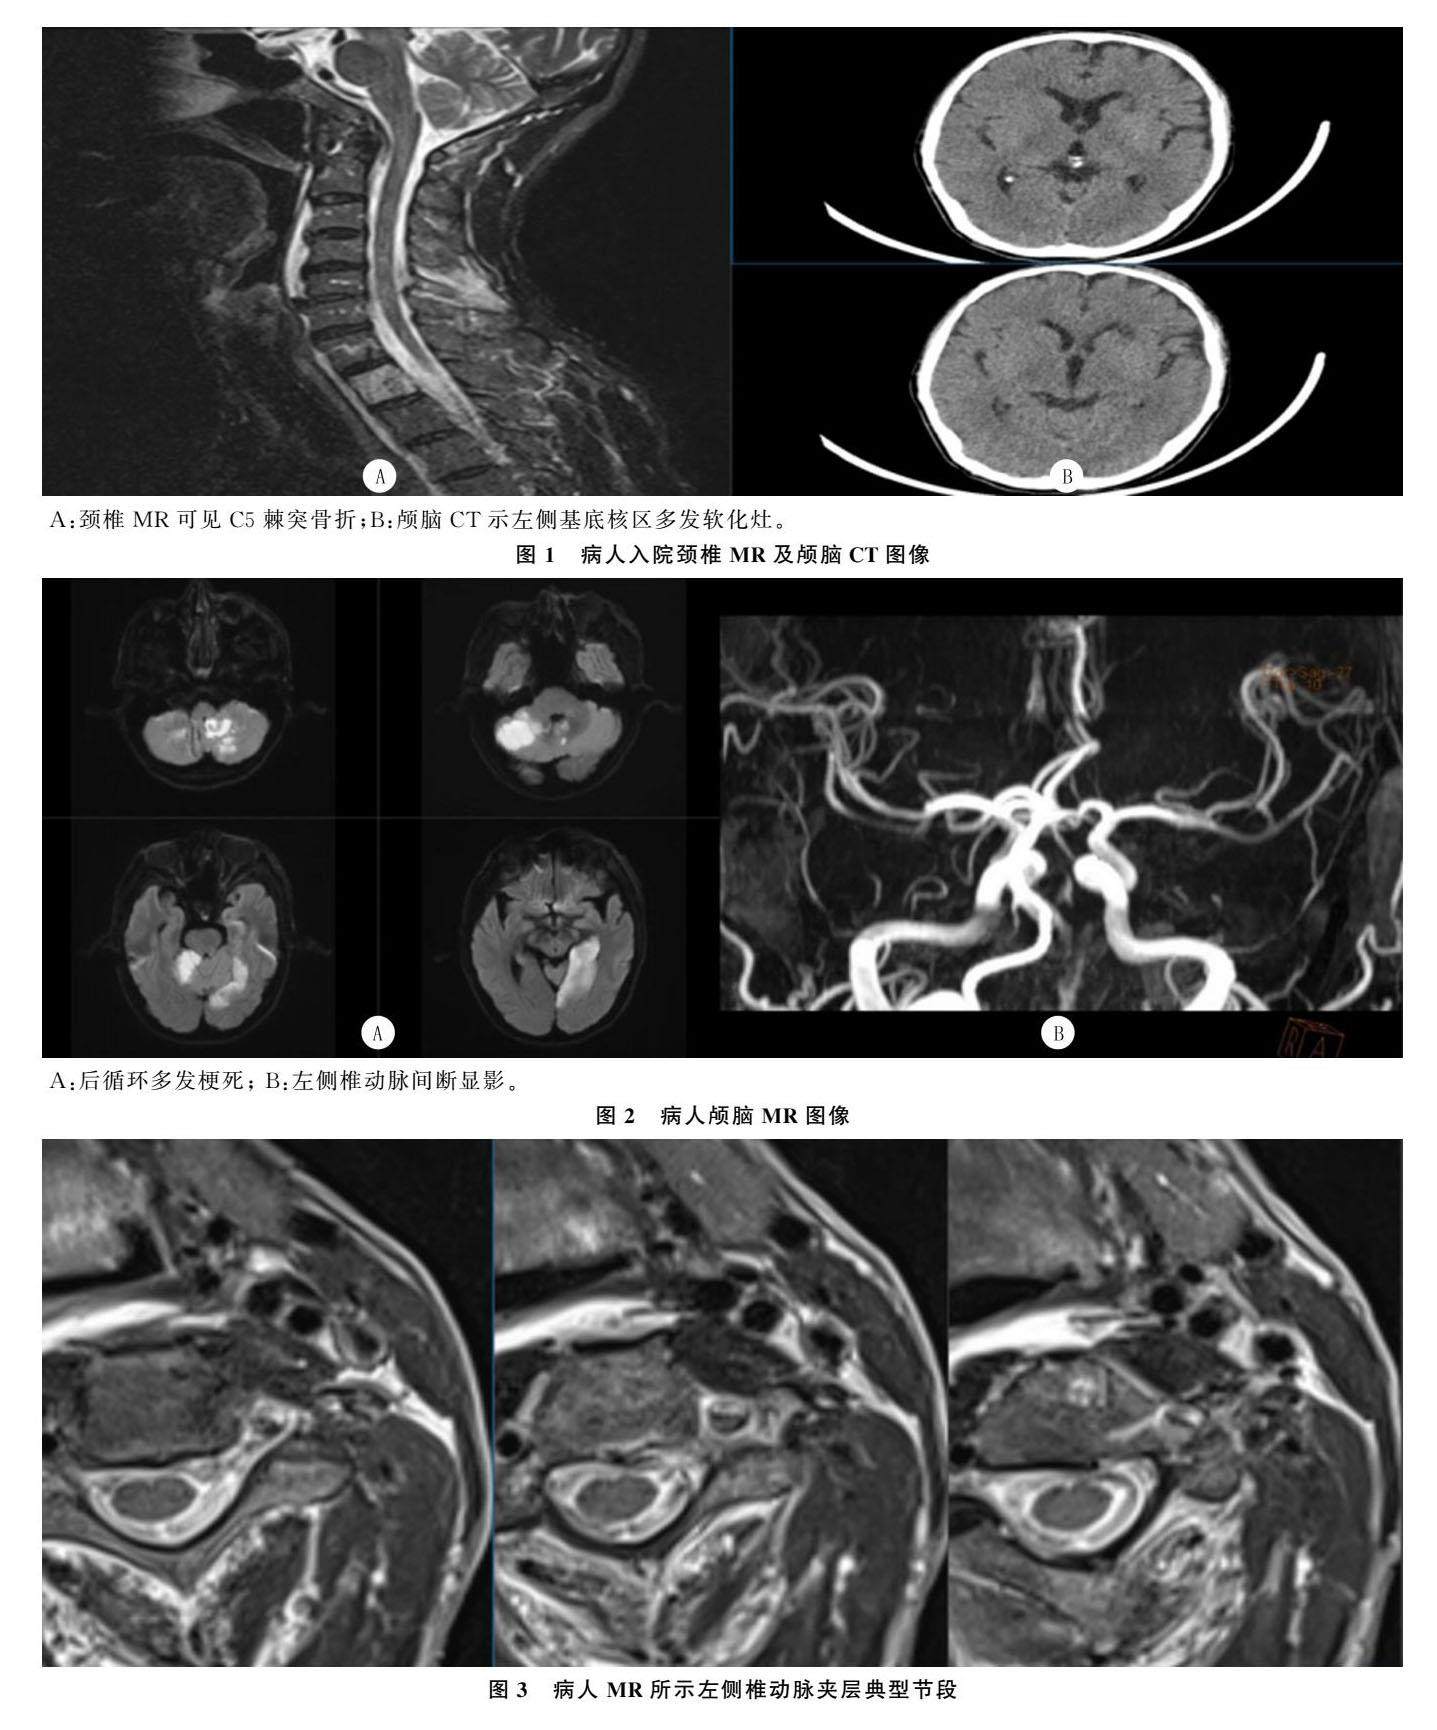

经验介绍 | 外伤性椎动脉夹层致迟发性脑梗死1例并文献复习

经验介绍 | 外伤性椎动脉夹层致迟发性脑梗死1例并文献复习